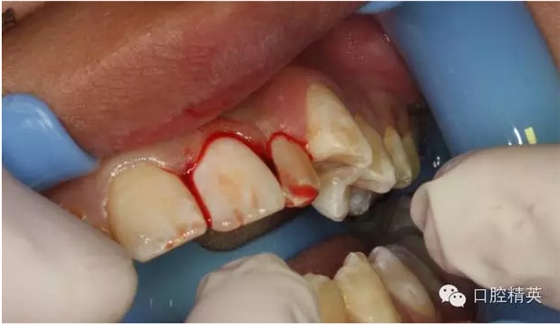

圖14.再植21離體牙

圖15.縫合初固定21